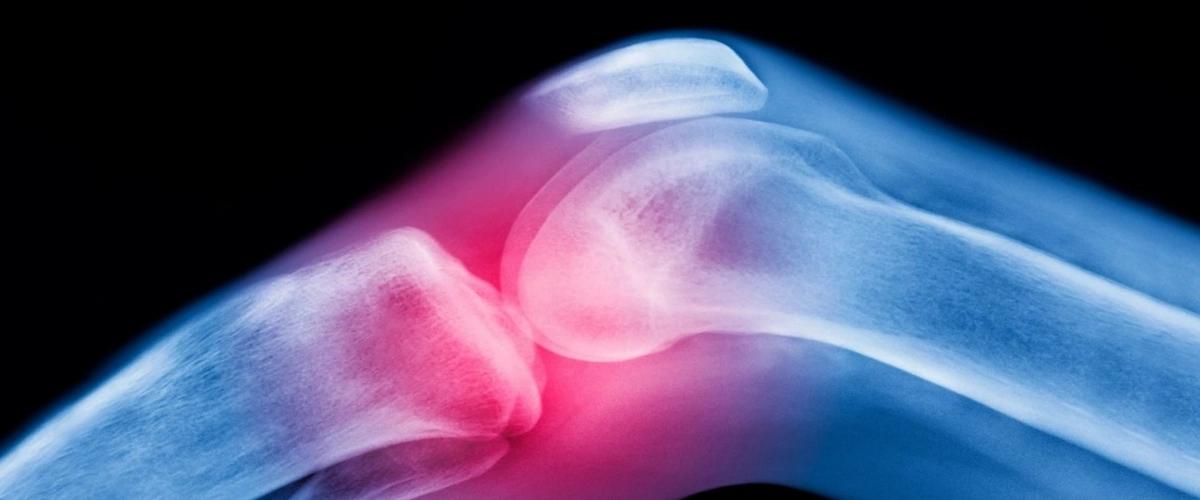

По статистике, с остеоартритом коленного сустава живут более 365 млн человек. Это хроническое дегенеративное заболевание с тяжелыми симптомами, поэтому миллионы пациентов полагаются на таблетки и инъекции стероидов, но они лишь временно маскируют симптомы. В новом исследовании, о котором пишет News Medical, ученые пригласили к участию 403 пациентов в возрасте от 40 до 90 лет и провели им эмболизацию коленной артерии.

Эмболизация коленной артерии уже применяется в клинической практике и предполагает блокировку кровотока в определенных ветвях артерий, которые образуют сеть вокруг коленного сустава. Блокировка кровотока нарушает постоянный цикл воспаления, разрушения хряща и сенсорных нервов.